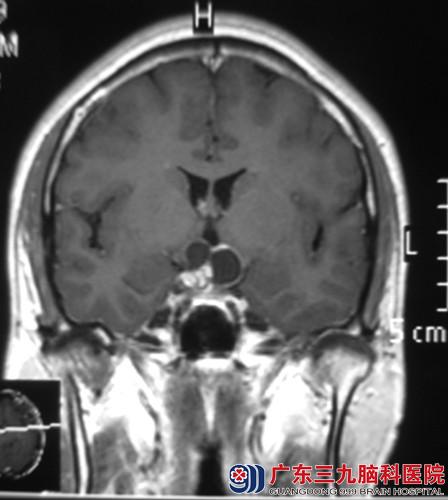

找到广东三九脑科医院综合神经外科 鲁明主任就诊,行头颅MR检查提示:鞍上示一囊实性占位病灶,大小约25.8*18.2*19.9mm,鲁明主任考虑颅咽管瘤可能性大。完善相关检查后,由鲁明主任主刀,在全麻下行经额前纵裂入路颅咽管瘤切除术,术中暴露双侧视神经及视交叉,见肿瘤位于鞍上,呈囊实性,在显微镜下予肿瘤切除,手术顺利结束,术后患者经专科治疗护理,小陈视力、视野正常,未出现任何术后并发症,康复出院。术后病理结果:颅咽管瘤。

术前 术后